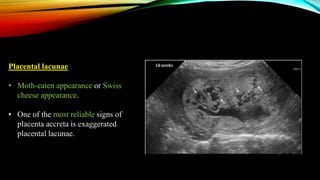

Placental lacunae

• Moth-eaten appearance or Swiss

cheese appearance.

• One of the most reliable signs of

placenta accreta is exaggerated

placental lacunae.